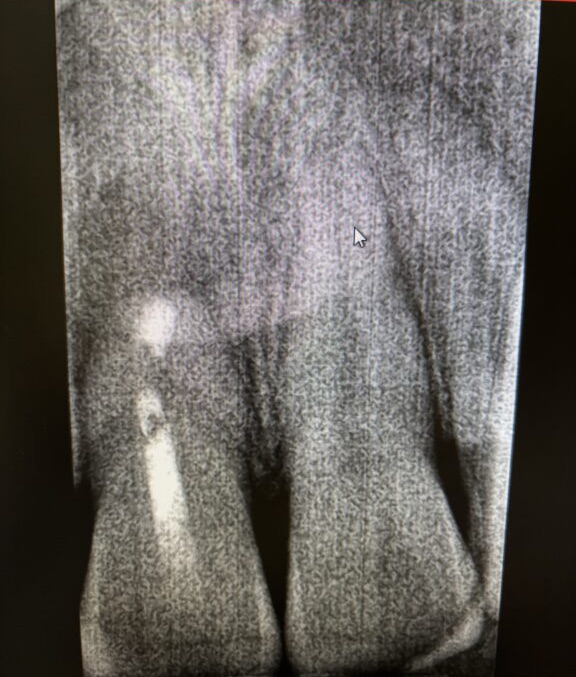

あらためて歯医者に行った。雨止んでて助かった。今日は先日手術してもらったところの経過観察だった。レントゲンを撮ってもらった。結果を待っているあいだ、後ろのほうで「11番、デンタルお願いします」というスタッフの声が聞こえた。ここでやることは全部デンタルだろと思った。

現状は良好とのことだった。先生の治療のおかげで、根元のない前歯がぎりぎり持ち堪えてくれていた。がんばれ〜! 歯!